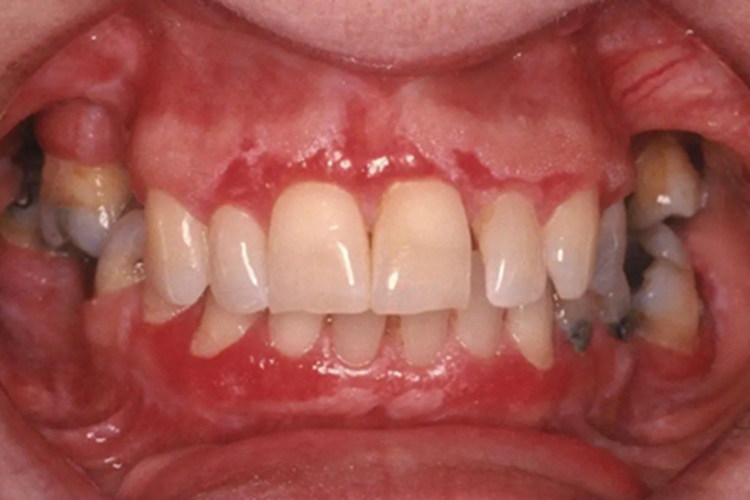

过敏性接触性口炎可累及牙龈部位,患者接触变应原后,经2-3天在接触部位发生病变,局部肿胀发红,或形成红斑,也可发生糜烂或溃疡,甚至组织坏死,患者自觉局部异物感,以及灼痛感。